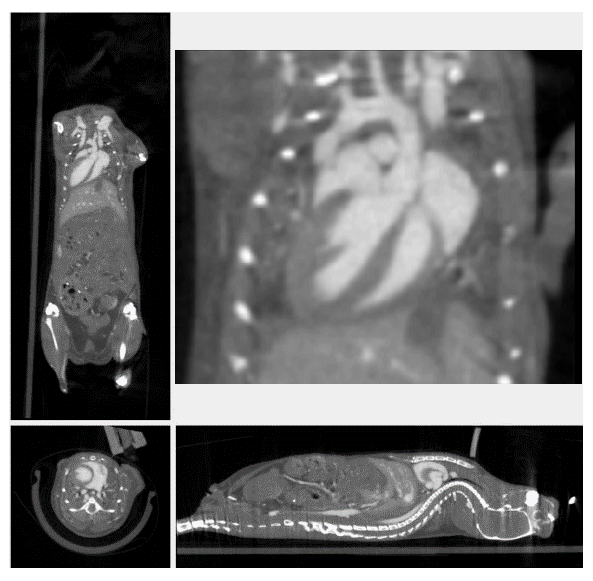

3、心血管研究

隨著造影劑及心跳門控技術的發(fā)展, micro-CT成為臨床前活體動物心臟研究的有利手段之一。micro-CT可以在相對短時間內(nèi)獲得心腔高分辨率的三維圖像,可以對心臟的形態(tài)學和整體心室收縮指數(shù)進行量化,如心搏量體積、射血分數(shù),心臟輸出量等。收縮功能異常常見于心血管疾病中,尤其在早期臨床表現(xiàn)中,而舒張功能的改善與生存時間的延長有關,因此,使用micro-CT評價舒張和收縮功能的評估是至關重要的,對心肺疾病的診斷、預后具有重要意義。

心臟門控成像

通過造影劑進行心臟結(jié)構成像和生理機能的監(jiān)測。對心肌肥大,心律不齊和心臟射血分數(shù)進行測定。